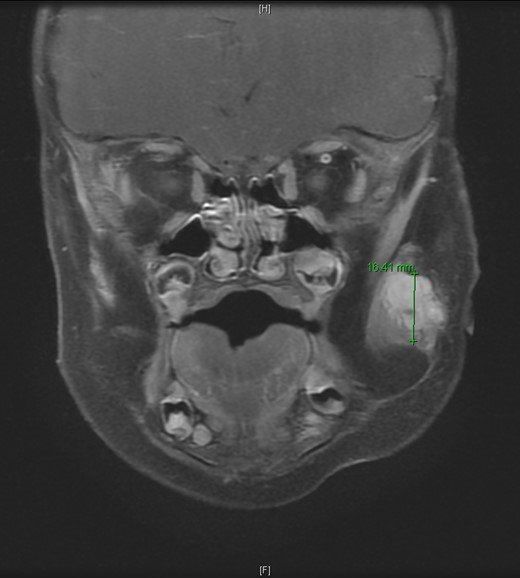

An 11-month-old male with a history of nasolacrimal duct stenosis and 4 mm thyroglossal duct cyst presented for evaluation of left facial swelling for 9 months. Approximately 6 months prior to admission, a mass was identified on the left cheek which had progressively increased in size over the past 2 months. The patient also had intermittent fevers the week prior to admission but was otherwise healthy. Baseline labs, including platelets, were within normal limits. On exam, he was found to have a firm, mobile, non-tender mass just inferior to the left zygomatic arch. Ultrasound revealed a vascularized solid lesion measuring 12 mm × 15 mm × 16 mm limited to the superficial soft tissues. MRI showed a multi-lobular mass with increased T2 signal centered within the left masseter and infiltrating signal in surrounding subcutaneous tissue (Fig. 1). The patient subsequently underwent ultrasound-guided core biopsy. The initial pathological diagnosis was consistent with TA, showing fibrovascular tissue containing compact nests of variably sized and ill-defined vascular channels. Immunohistochemistry staining showed the endothelial cells to be diffusively reactive for CD34 and CD31, partially reactive for D2-40, and negative for GLUT-1. However, upon further review, KHE was favored given the solid and infiltrative components on MRI, normal overlying skin on exam, and location of the lesion within subcutaneous fat. Accordingly, low-dose daily aspirin was prescribed prophylactically to prevent KMP. An MRI 2 months later, along with serial ultrasound images in the ensuing 26 months, showed no further growth (Fig. 2). His parents noted intermittent painless changes in size that did not seem to be related to any stimulus and returned to baseline size within hours. Surgical intervention at 3 years old is anticipated.

T2-weighted MRI 2 months later revealed a 14.5 mm × 14.1 mm × 15.95 mm mass partially involving the masseter muscle with no internal vascular flow voids.